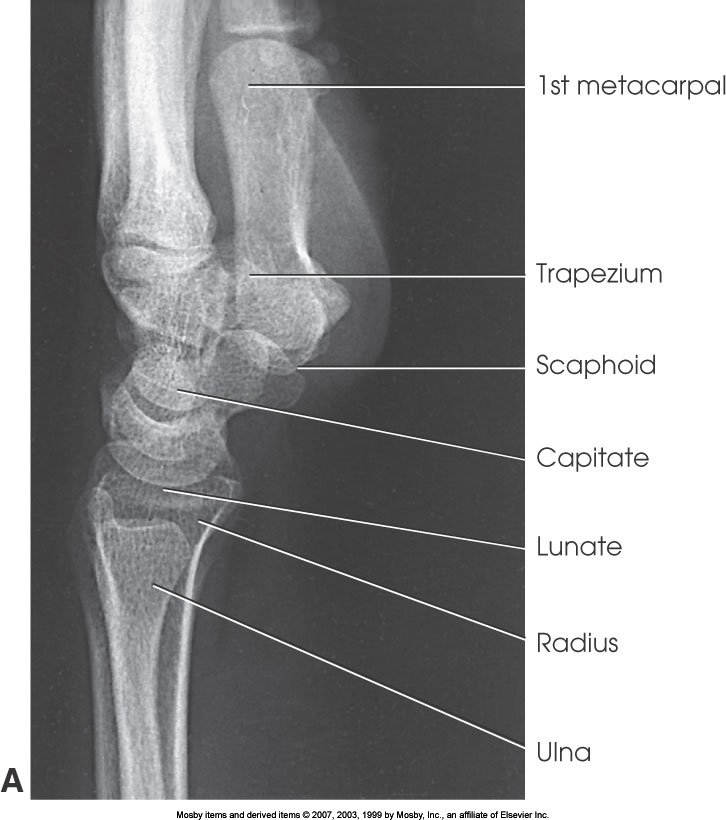

What position is demonstrated?

Lateral Wrist